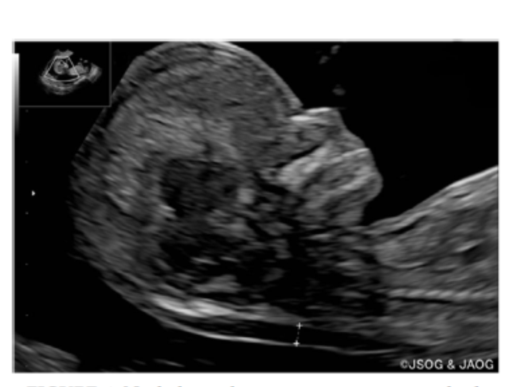

3、在以下情况下准确测量NT值(B级)。

(1)在孕11~13周+6天时进行测量。

(2)超声图像应充分放大,扫描胎儿的上半身(图1)。

(3)在中矢状部测量。

图1